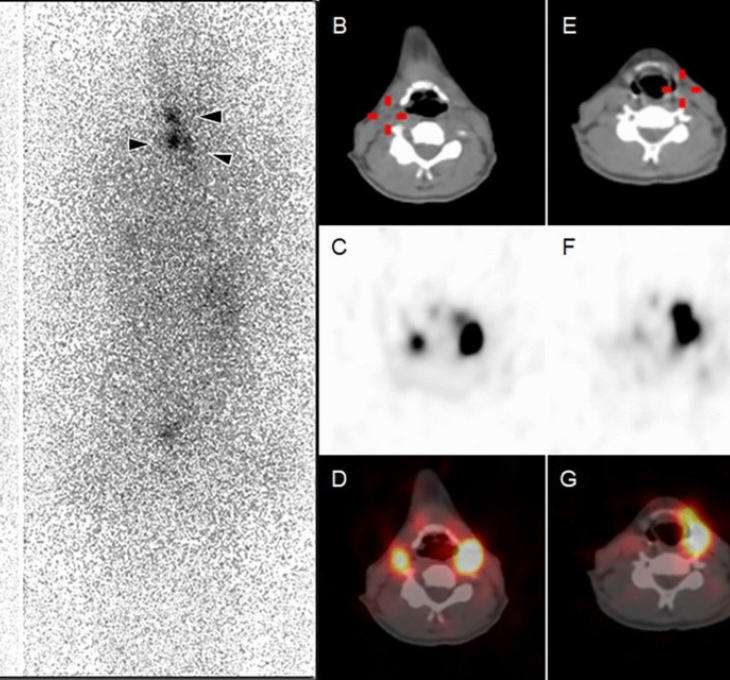

I-131 Scan

Performed in thyroid cancer patients after thyroid surgery or during follow-up.

Parathyroid Scan

Used to identify parathyroid gland abnormalities causing elevated calcium levels.